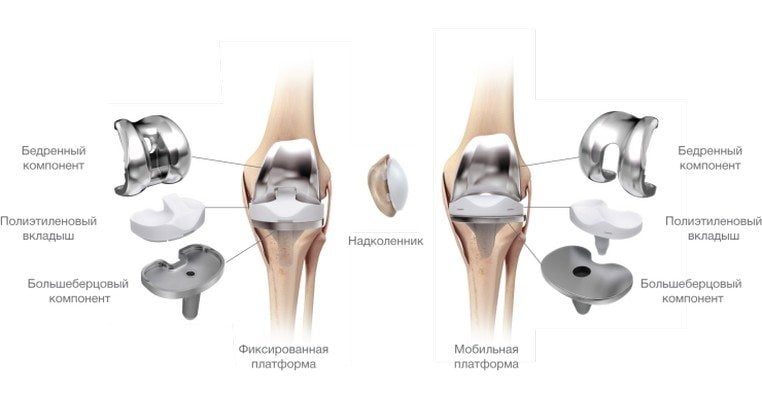

- эндопротезирование. Эта операция производится в том случае, если сочленение или его элементы требуют полной замены. Протез изготавливается из сплава металлов – титана. Несмотря на то что операция требует длительного периода восстановления, эффект от нее весьма продолжителен – до 20 лет.